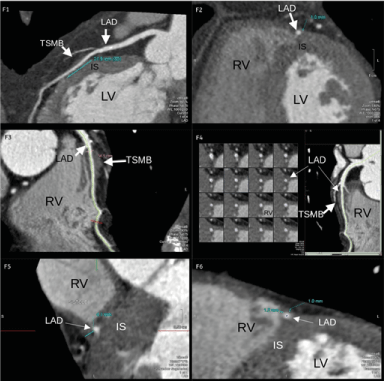

Figure 3. Coronary CT images. CASE 1 (F1-F2) and CASE 3 (F3-F6). F1. Longitudinal section of the tunneled segment in the interventricular septum of the anterior descending artery where the radiologist measured the MB length (21.5 mm). F2. Cross section of the tunneled segment where the depth (1 mm) and distance to ventricular cavities are measured. F3. Longitudinal section of the MB with tunneled segment 56.5 mm deeper proximally and closer to RV distally. F4. Transversal and longitudinal sections showing the location of the tunneled segment of the MB in the interventricular septum. F5 and F6. Extended cross sections of the MB where the maximum depth of 4.1 mm was measured (F5) and the minimum distance to the right ventricle of 1.2 mm at distal level where the depth was only 1 mm (F6). LV: Left Ventricle, IS: Interventricular septum, RV: Right Ventricle, TSMB: Tunneled Segment Myocardial Bridge, LAD: Left Arterial Descending.

In cases 1 and 2, the duration of absolute and relative DCC was shorter, mainly systolic. Nevertheless, for case 3, with a longer MB length (61 mm), the milking effect remained until the end of diastole (whole cycle) producing a compressive stenosis of greater severity (which resembled a fixed stenosis) (Table 2). In these severe cases, intracoronary imaging was important to identify other factors such as coronary spasm, endothelial dysfunction, and atherosclerotic disease that could explain the greater symptomatology of patient 3. In addition, case 3 presented marked distal kinking as it abruptly penetrated the interventricular sulcus, further increasing the resistance to flow. cCT confirmed greater length and depth of the MB in case 3 with a course very close to the right ventricle (Figure 3).

Anatomically and angiographically, patient 3 with the longer MB was the one to present the worst clinical severity. Additionally, case 3 presented higher maximum epicardial depth and more tortuosity. Studies have directly related length and especially depth with a higher degree of DCC and severity of angina [26-28,30-34], which would explain the greater symptoms of patient 3. However, no relationship with major adverse events has been demonstrated [35].